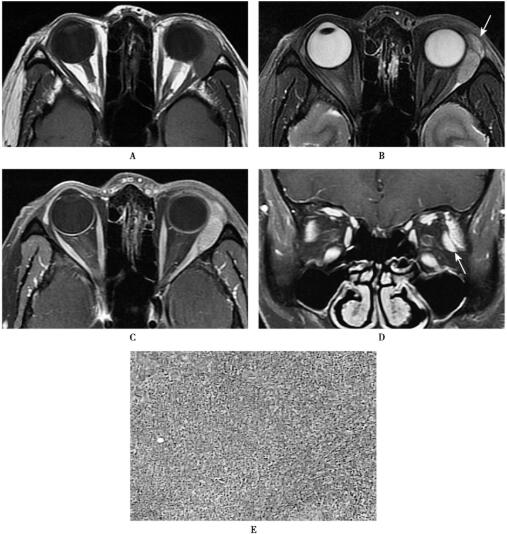

应用3.0TMRI超导型全身磁共振扫描仪(HDx,GE),8通道头线圈,SE体轴横断位T1WI[TR/TE=(360~400ms)/(11~13ms)],FSE横断和冠状位脂肪抑制T2WI[TR/TE=(3000~6000ms)/(42~109ms)],3mm层厚,1mm间隔,512×512矩阵,200mm视野。应用钆喷酸葡胺(剂量0.1mmol/kg体重)行MRI增强扫描,注射流率2.5ml/s,获得体轴横断、冠状和矢状位T1WI。磁共振表现见图1。

图1 左眼眶淋巴组织增生

(左眼眶)淋巴组织增生。HE染色(×40倍),镜下可见弥漫增生的淋巴组织。